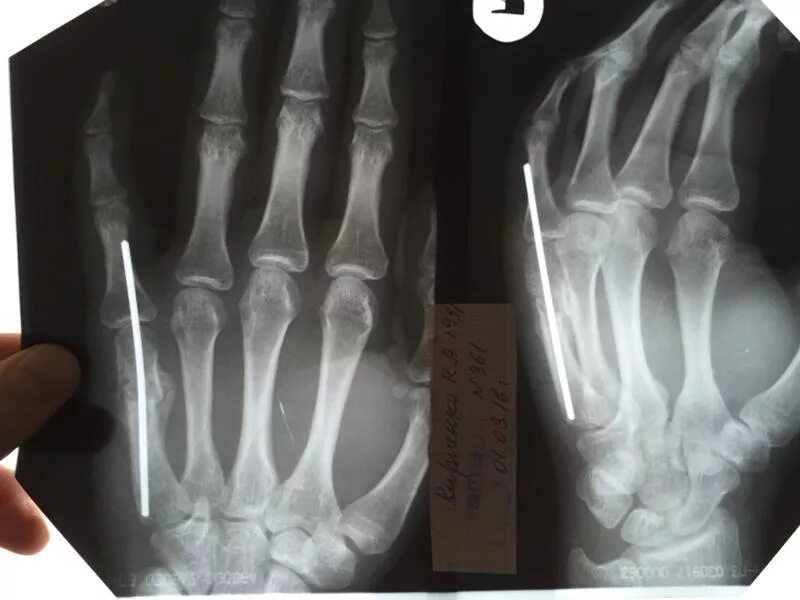

Остеосинтез пястной кости спицами. перелом пястной кости спицы. перелом 3 пястной кости левой руки.

Остеосинтез 2 пястной кости. остеосинтез 5 пястной кости. остеосинтез 5 пястной кости кисти спицей. остеосинтез пястной кости спицами.

Перелом 5 пястной кости кисти. остеосинтез 2 пястной кости. остеосинтез 5 пястной кости. спица киршнера перелом 5 пястной кости.

Остеосинтез пястных костей спицами. остеосинтез 5 пястной кости спицей киршнера. спицы при переломе 5 пястной кости. остеосинтез пястной кости спицами.